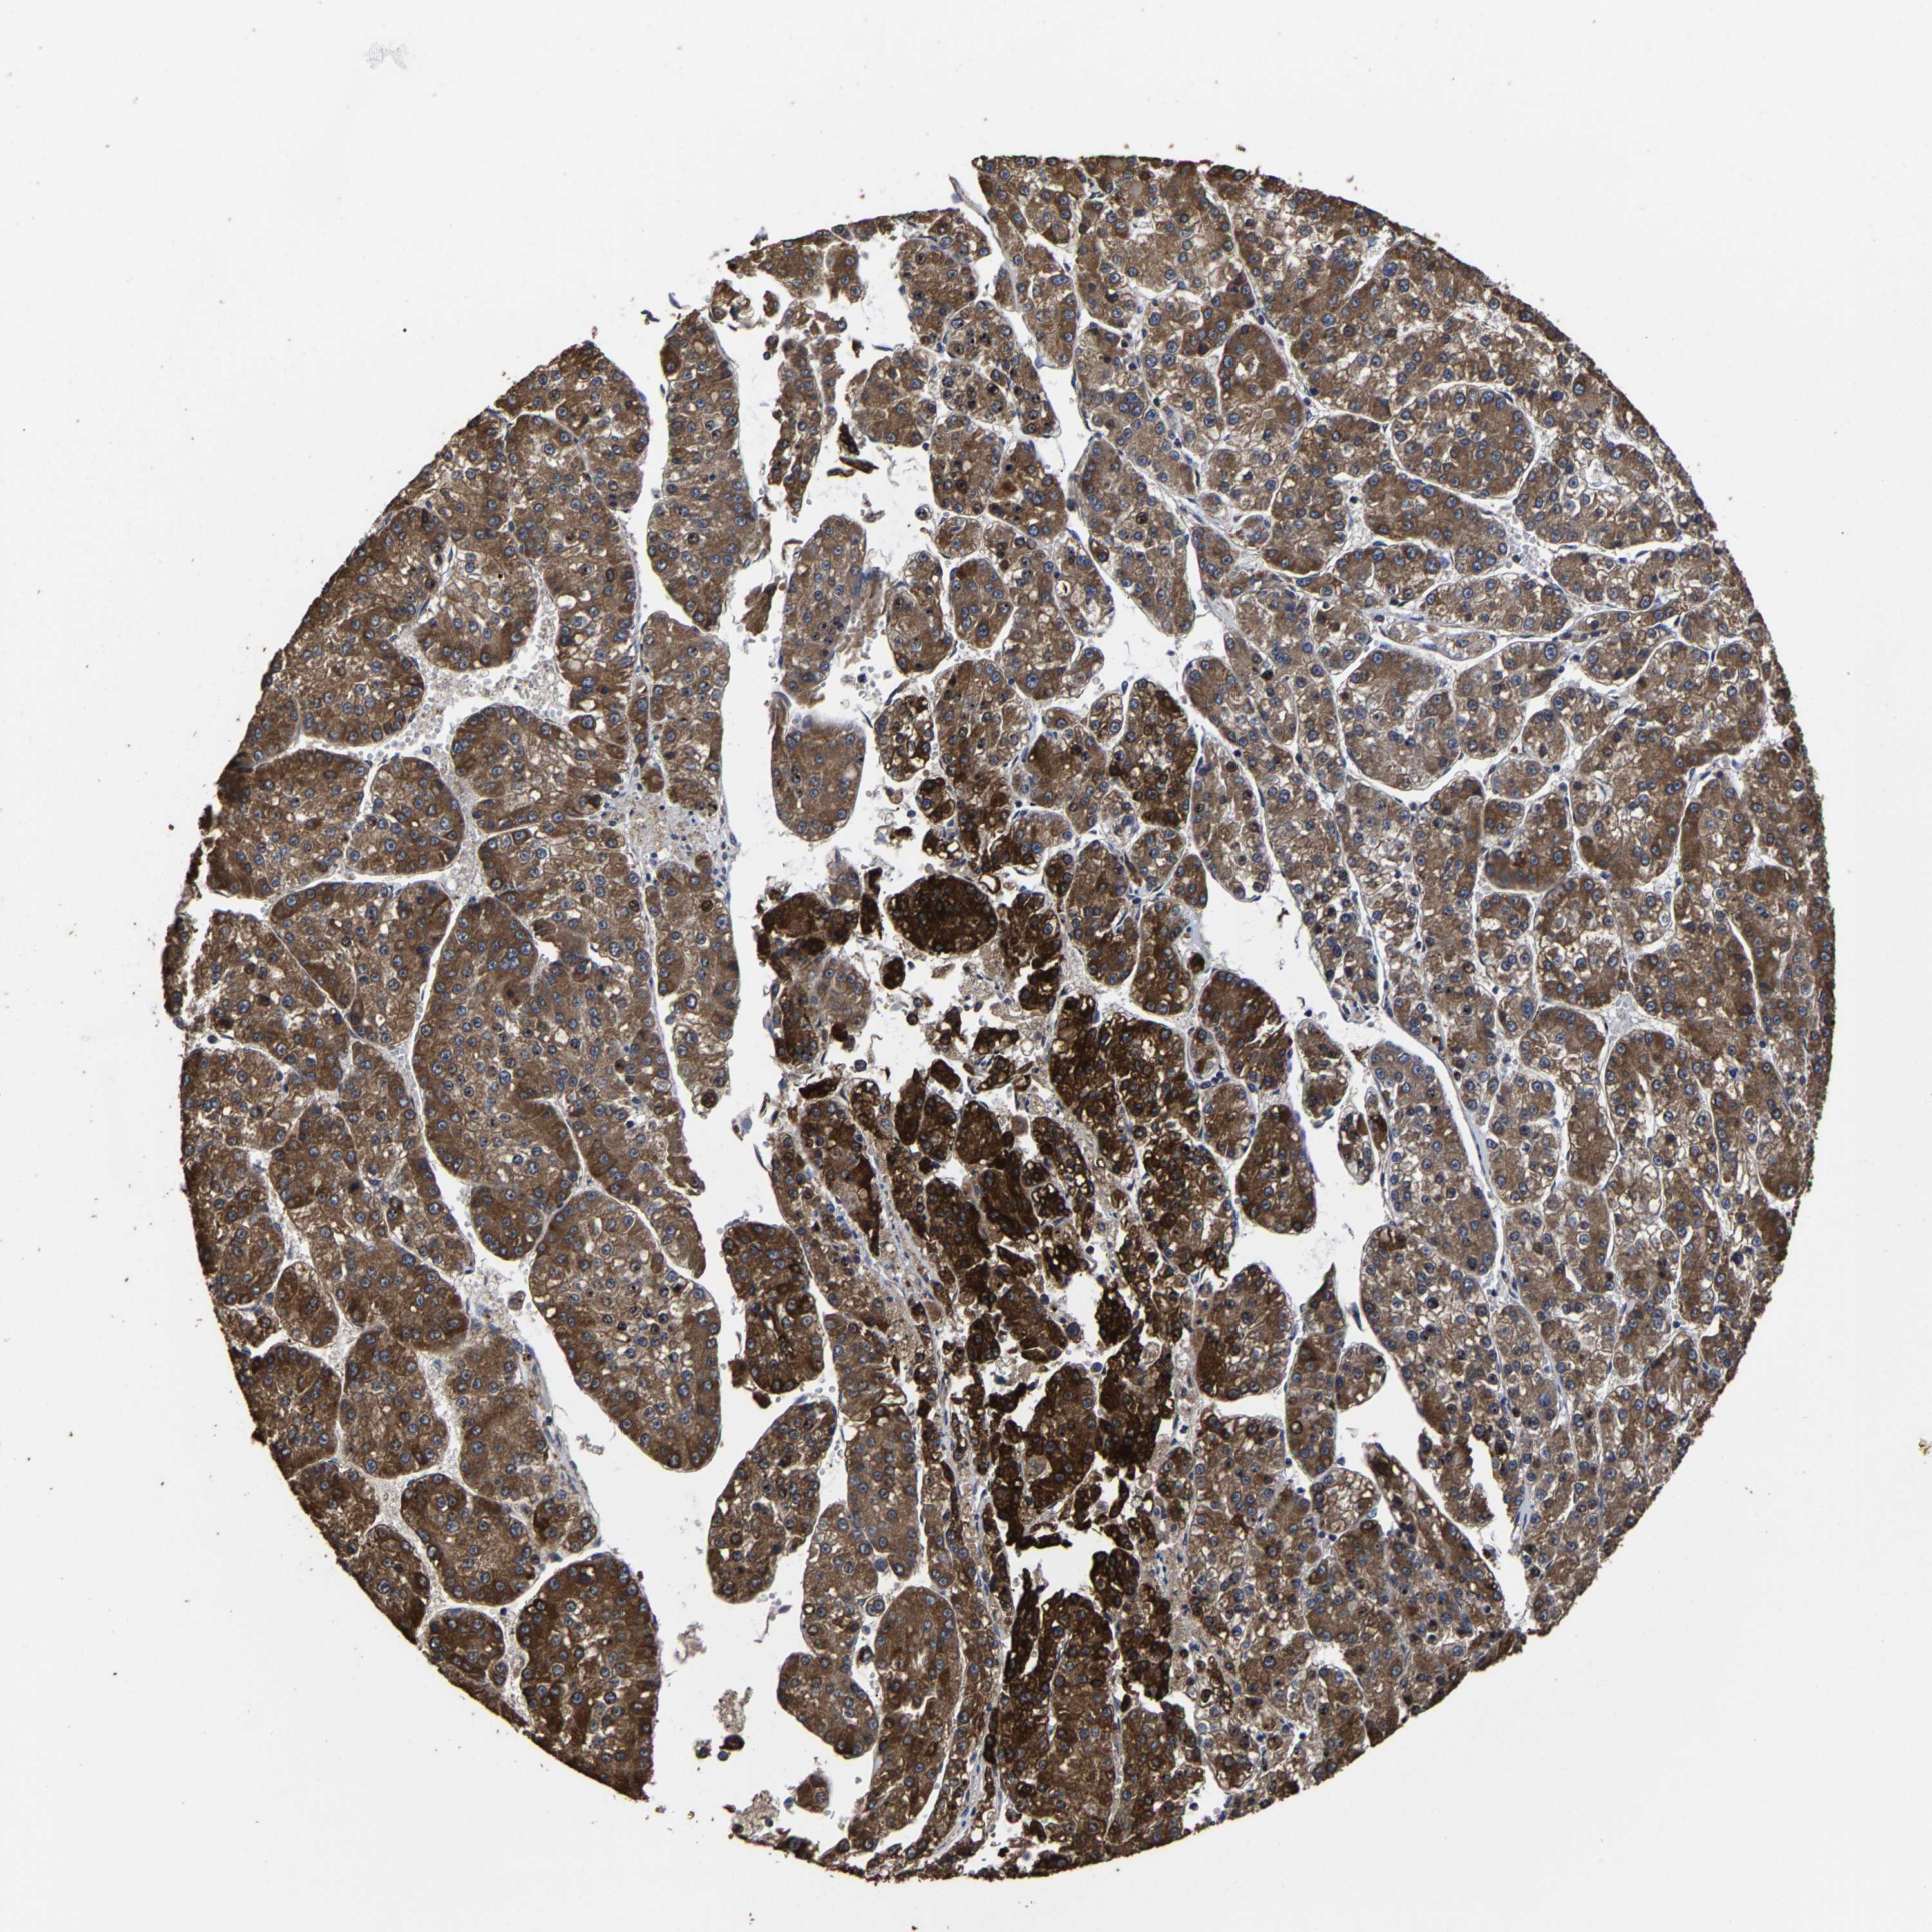

LIVER CANCER